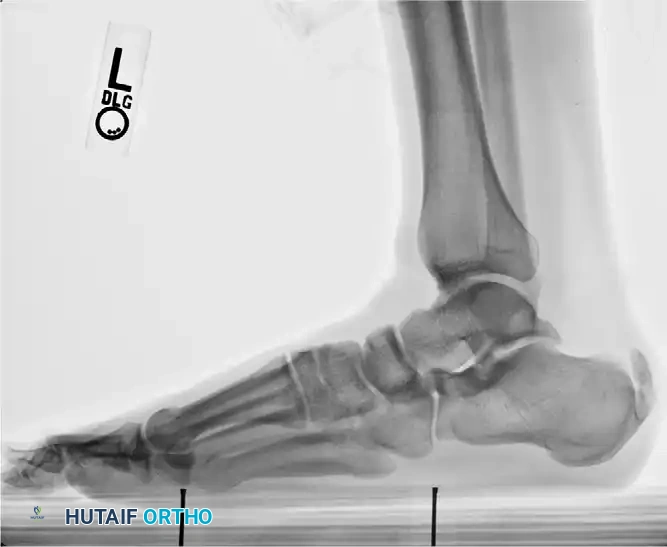

Radiographic Evaluation

Standard weight-bearing radiographs of the foot and ankle are mandatory. A standing lateral view of the heel is particularly useful for evaluating:

* The presence and size of a Haglund deformity (posterosuperior calcaneal prominence).

* Intratendinous calcific spurs extending proximally from the insertion.

* Chauveaux-Liet angle or parallel pitch lines to quantify the deformity.